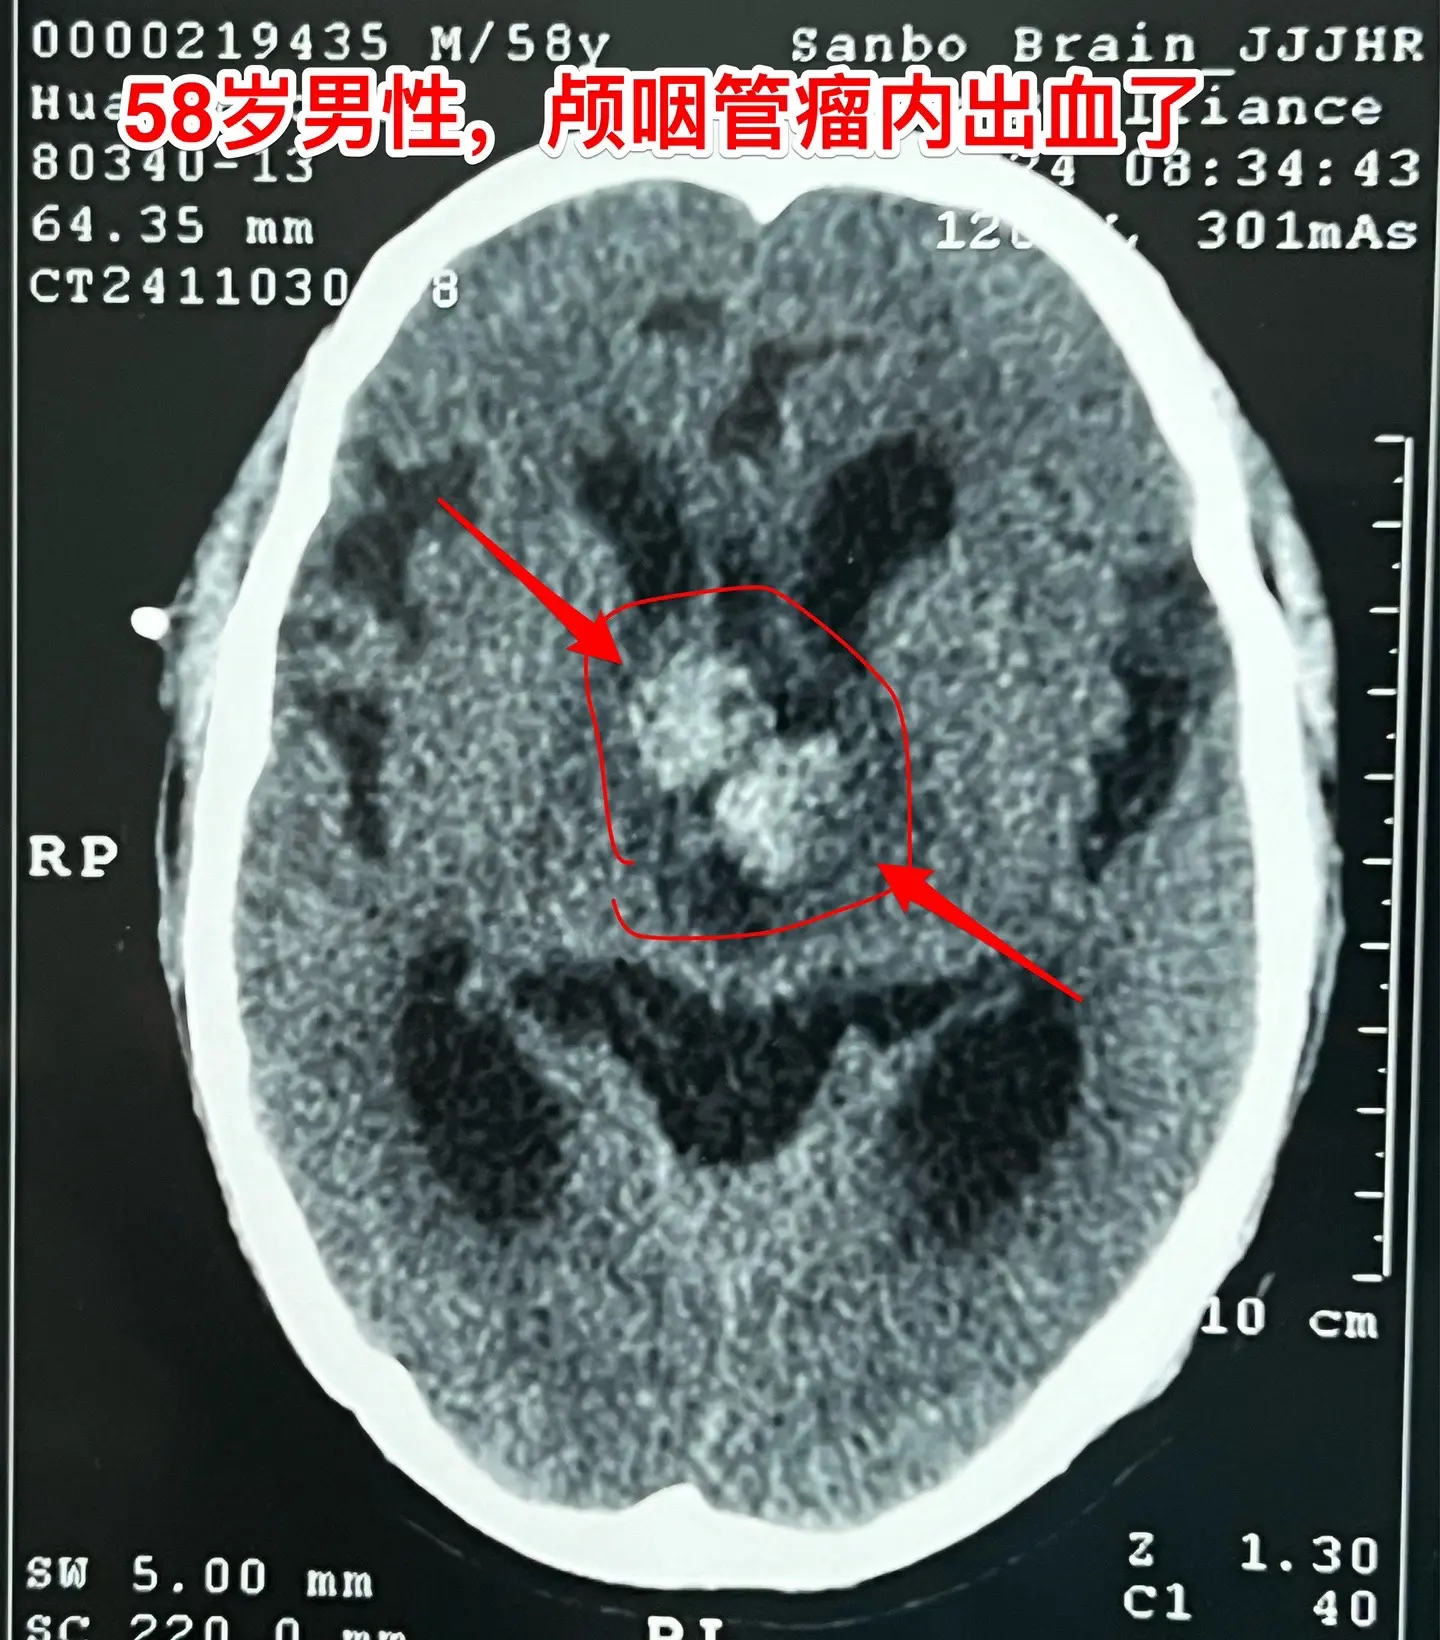

颅咽管瘤内出血(瘤卒中)属于罕见现象。有些脑部肿瘤容易出血,称之为瘤卒中,比如垂体瘤(属于良性肿瘤)和高级别胶质瘤,而颅咽管瘤发生瘤卒中的可能性却很小很小。 58岁的南通市男性,九年前体检发现鞍区病变,无任何症状,一直没有做任何治疗。四个月前开始出现头晕、行走不稳,同时还有思维糊涂,有一次癫痫发作。这次到医院检查就发现鞍区肿瘤增大了,而且导致了脑积水。 2024.9在外院作了脑积水的分流手术,没有切除肿瘤。手术后行走不稳症状有好转,但是思维糊涂症状却越来越严重,有时感头痛。 2024.10到我科住院,病人不仅仅是思维糊涂,还出现头痛症状。行头部CT检查提示颅咽管瘤内出血了。 2024年11月14日作了开颅手术。切除肿瘤过程中可以看见肿瘤内有陈旧出血。病理报告为乳头型颅咽管瘤。乳头型颅咽管瘤出现瘤卒中的概率是很低的,我曾经在2008年报告了一例。造釉细胞性颅咽管瘤几乎不出现瘤卒中。 这个病人的脑积水是由颅咽管瘤引起的,所以,切除颅咽管瘤后脑积水自然就会缓解。希望他的症状会越来越改善。颅咽管瘤脑积水瘤卒中